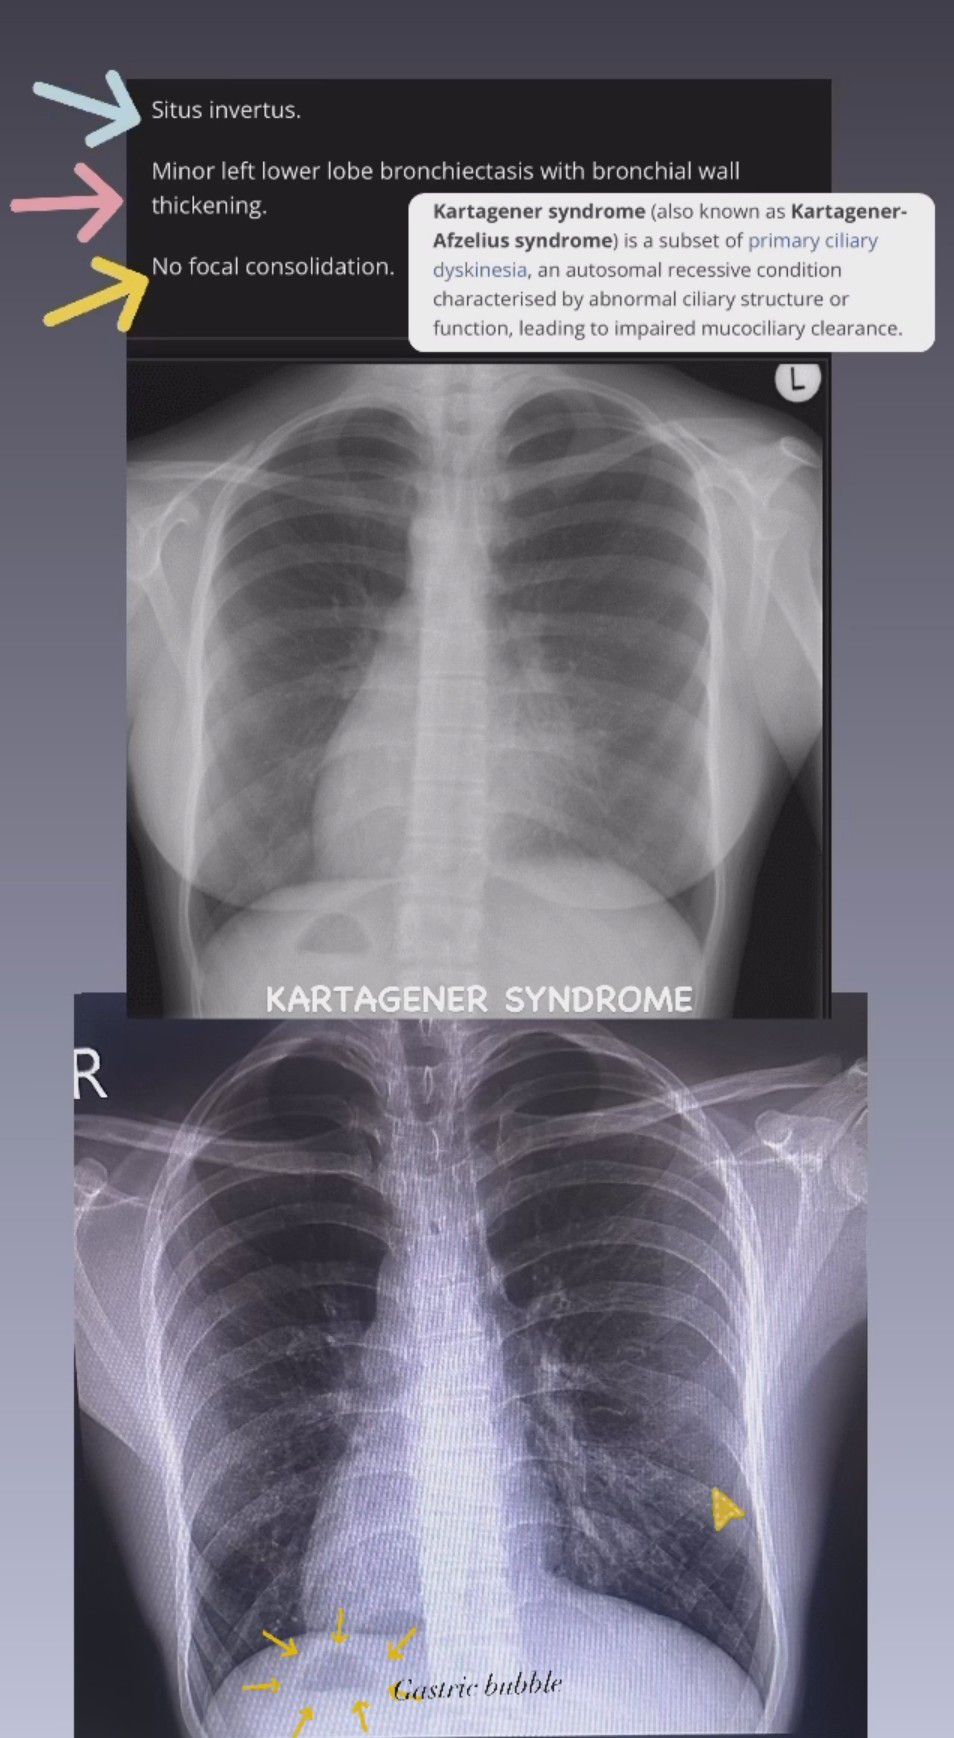

Kartagener Syndrome